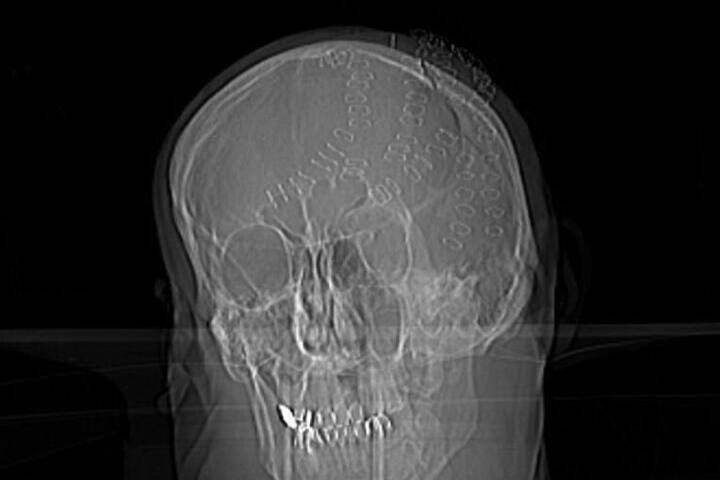

Врачи нейрохирургического отделения Владивостокской клинической больницы №2 провели уникальную операцию по спасению 50-летнего мужчины, получившего тяжелейшую травму головы в результате удара топором на острове Попова. Об этом сообщили в пресс-службе учреждения.

По данным медиков, у пострадавшего были зафиксированы травматическое субарахноидальное кровоизлияние, ушиб мозга, множественные оскольчатые и линейные вдавленные переломы теменных костей, а также рубленые раны головы. Пострадавший в критическом состоянии был эвакуирован катером и доставлен во Владивосток, где его уже ожидала бригада скорой помощи.

Состояние мужчины на момент поступления оценивалось как крайне тяжелое. Из-за массивной кровопотери он впал в геморрагический шок, угрожавший жизни. Операция включала удаление вдавленных фрагментов черепа, остановку кровотечений и реконструкцию костной структуры головы. Хирургическое вмешательство продолжалось несколько часов.